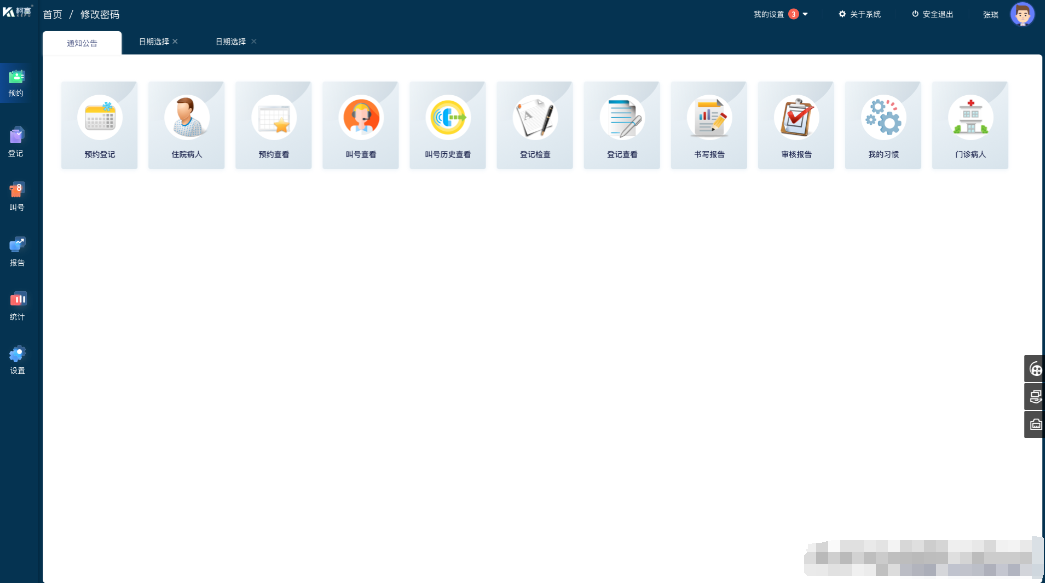

医院信息管理系统(HIS)是现代化医院运营的基础,它涵盖了医院各个部门的业务流程,包括门诊、住院、药房、财务等。

在门诊管理方面,HIS 系统可以实现挂号、分诊、医生工作站等功能。患者可以通过线上或线下渠道进行挂号,系统会根据患者的病情和需求自动分诊到相应的科室和医生。医生在工作站中可以查看患者的基本信息、病历记录、检查检验报告等,方便快速地做出诊断和治疗方案。

住院管理是 HIS 系统的重要组成部分。从患者入院登记、床位分配到医嘱下达、费用结算,HIS 系统都能进行高效的管理。护士可以通过系统实时查看患者的生命体征、医嘱执行情况等,确保患者得到及时的护理和治疗。同时,系统还可以对住院费用进行自动核算,避免了人工计算的错误和繁琐。